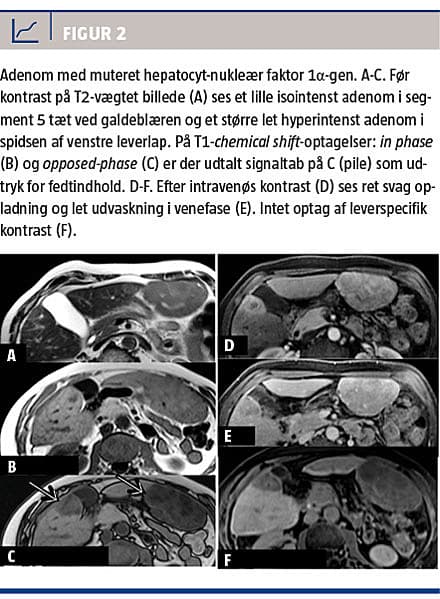

Ved MR-skanning før kontrast er adenomer iso- eller hyperintense på T2-vægtede billeder, og på T1-vægtede billeder kan de have alle signalintensiteter afhængigt af indhold af fedt, blødning og nekrose [19]. De udviser forskellige opladningsmønstre, og en analyse af signalintensitet og opladningsmønster muliggør differentiering mellem forskellige undertyper: inflammatoriske adenomer (Figur 1) har et højt T2-signal med endnu højere signal i tumorperiferien, forårsaget af dilaterede sinusoider. På T1-vægtede billeder er de iso- eller lethyperintense, de er uændrede ved chemical shift-optagelser, da de ikke indeholder fedt og har kraftig arteriel opladning, som persisterer i venefase og sen fase.